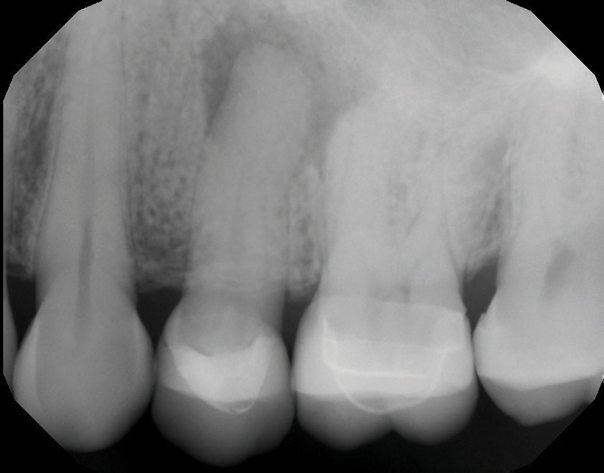

A 62-year-old female patient presented to the endodontist on referral from her general dentist to evaluate tooth No. 13 with visible radiographic pathology. She denied dental pain, but reported long-standing symptomatic sinusitis of unknown origin that was not responsive to over-the-counter treatments, including nasal sprays and decongestants. Clinical examination found that tooth No. 13 was unresponsive to pulp sensitivity tests and non-tender to percussion and palpation. A full-coverage ceramic crown was intact, and adjacent soft tissues were unremarkable.

Periapical and CBCT imaging confirmed the presence of apical pathology, as well as a dramatic sinus communication with MSEO (Figure 1 and Figure 2). The diagnosis for tooth No. 13 was pulpal necrosis with asymptomatic apical periodontitis. NSRCT was completed (Figure 3). At the patient's 1-year follow-up appointment, tooth No. 13 remained asymptomatic, her sinusitis was resolved, and complete radiographic healing of both periapical pathology and the MSEO was noted (Figure 4).

Fig 1. Case 1. Preoperative periapical radiograph showing periapical pathology associated with tooth No. 13.

Figure 1